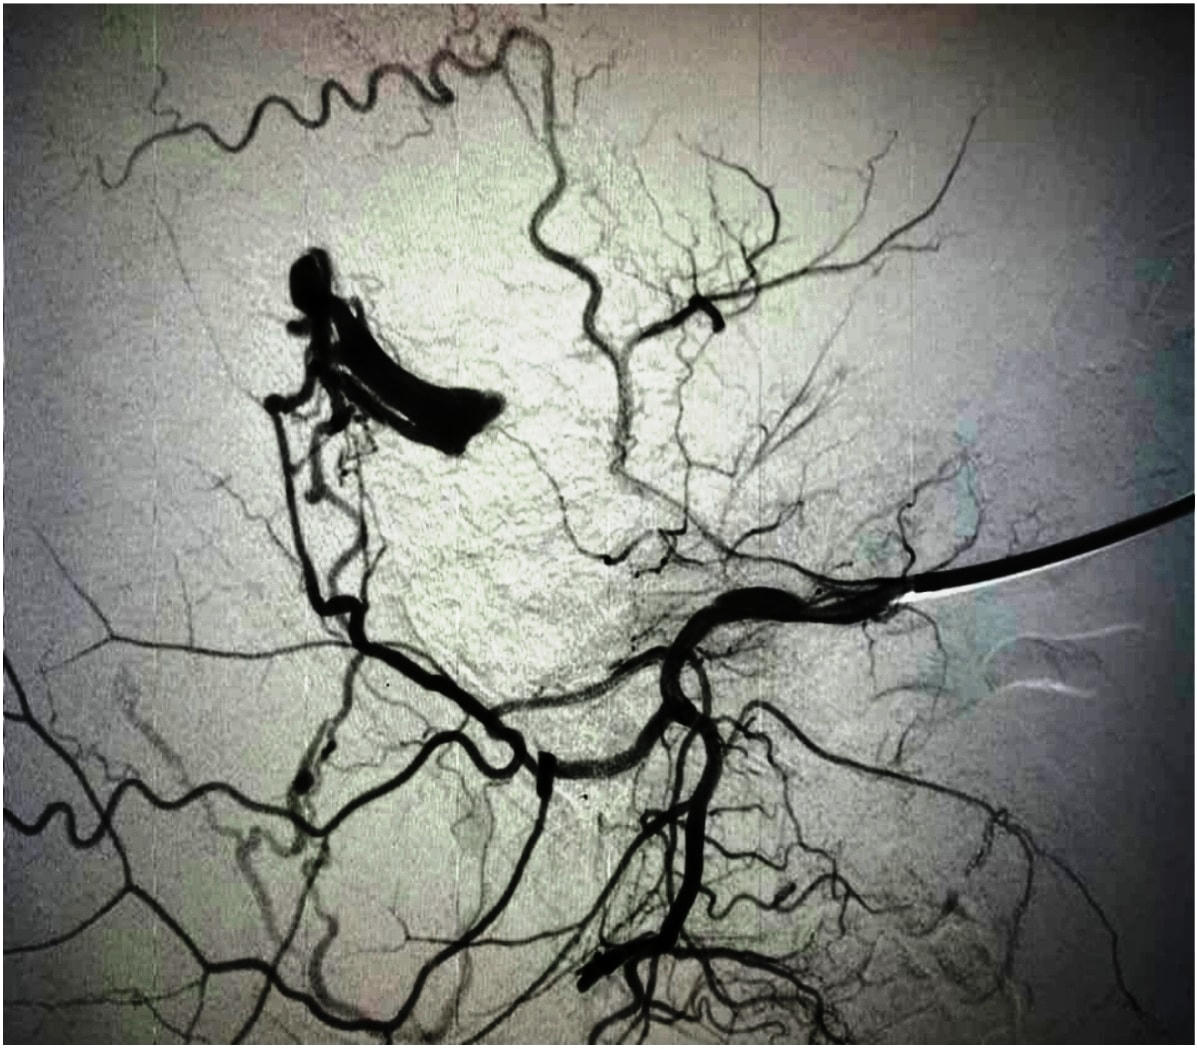

Bênh nhân sau đó được nhập viện khoa Nội tim mạch BVĐK Quảng Nam để chụp mạch máu não nhằm chẩn đoán và lên chiến lược điều trị. Kết quả chụp mạch máu não chẩn đoán dò động tĩnh mach màng cứng từ động mạch cảnh ngoài bên trái vào xoang sigma bên trái kèm tắc xoang sigma trên và dưới vị trí dò, phân độ rò màng cứng theo Cognard typ IV, nguy cơ cao xuất huyết não, có chỉ định điều trị nút mạch để tắc dò.

Bệnh nhân sau đó đã được điều trị can thiệp tắc vị trí dò bằng coils và bằng hạt nhựa. Kết quả chụp kiểm tra sau can thiệp nhận thấy tắc hoàn toàn các nhánh dò từ động mạch cảnh ngoài vào xoang sigma. Bênh nhân sau đó được theo dõi, điều trị tại khoa nội tim mạch và đến nay bệnh nhân đã xuất viện với tình trạng khỏe mạnh và hoàn toàn không để lại di chứng.